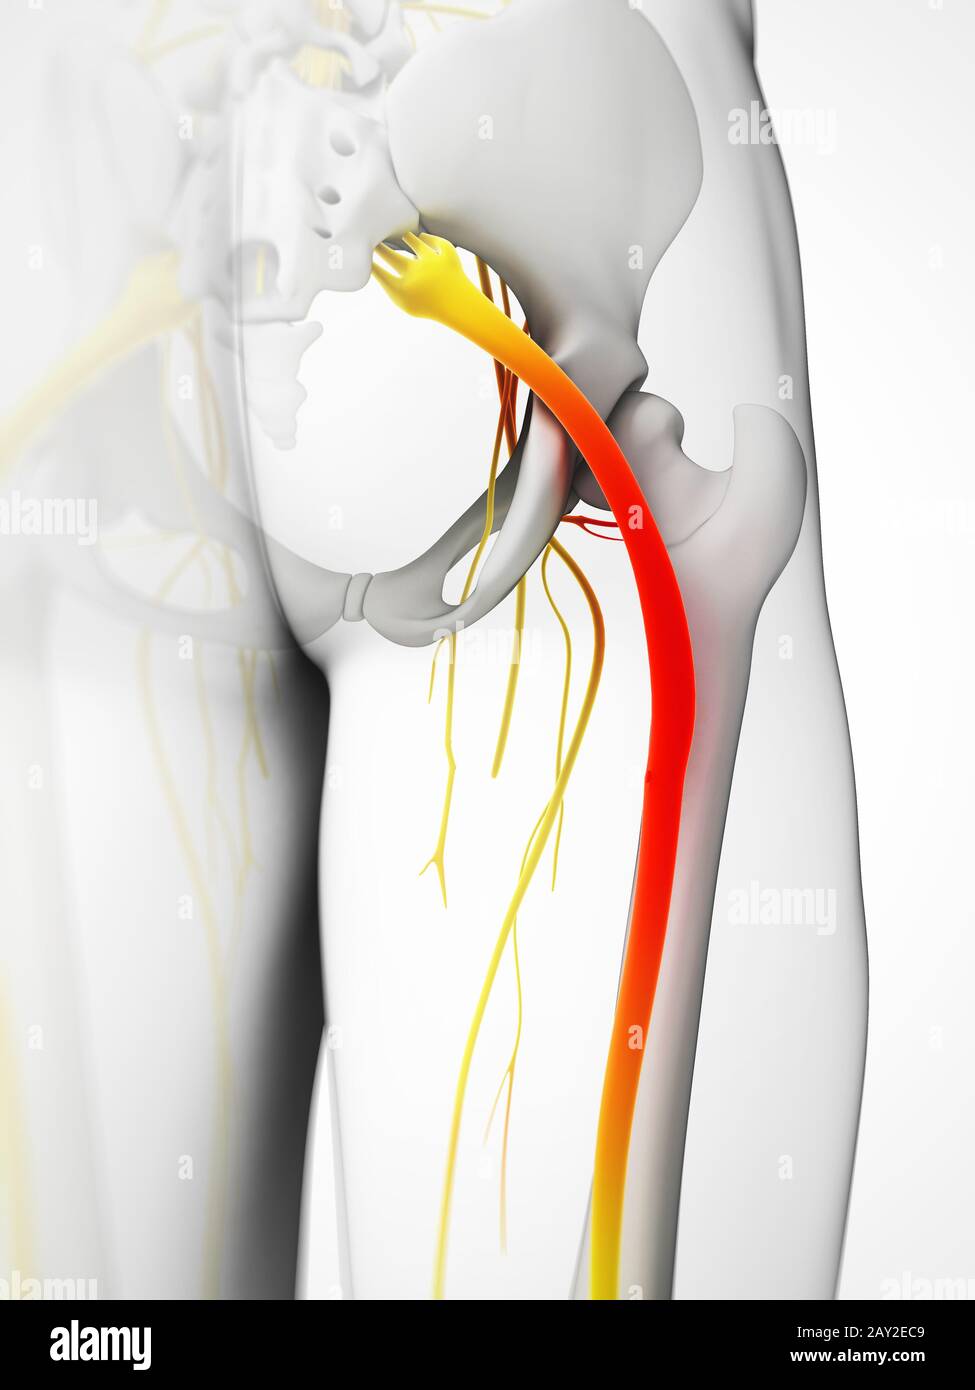

Douleur du nerf sciatique, illustration Banque D'Imageshttps://www.alamyimages.fr/image-license-details/?v=1https://www.alamyimages.fr/douleur-du-nerf-sciatique-illustration-image353192503.html

Douleur du nerf sciatique, illustration Banque D'Imageshttps://www.alamyimages.fr/image-license-details/?v=1https://www.alamyimages.fr/douleur-du-nerf-sciatique-illustration-image353192503.htmlRM2BEH8HY–Douleur du nerf sciatique, illustration

Douleur du nerf sciatique, illustration Banque D'Imageshttps://www.alamyimages.fr/image-license-details/?v=1https://www.alamyimages.fr/douleur-du-nerf-sciatique-illustration-image353192461.html

Douleur du nerf sciatique, illustration Banque D'Imageshttps://www.alamyimages.fr/image-license-details/?v=1https://www.alamyimages.fr/douleur-du-nerf-sciatique-illustration-image353192461.htmlRM2BEH8GD–Douleur du nerf sciatique, illustration

Rendu 3d illustration - nerf sciatique Banque D'Imageshttps://www.alamyimages.fr/image-license-details/?v=1https://www.alamyimages.fr/rendu-3d-illustration-nerf-sciatique-image343647929.html

Rendu 3d illustration - nerf sciatique Banque D'Imageshttps://www.alamyimages.fr/image-license-details/?v=1https://www.alamyimages.fr/rendu-3d-illustration-nerf-sciatique-image343647929.htmlRM2AY2EC9–Rendu 3d illustration - nerf sciatique